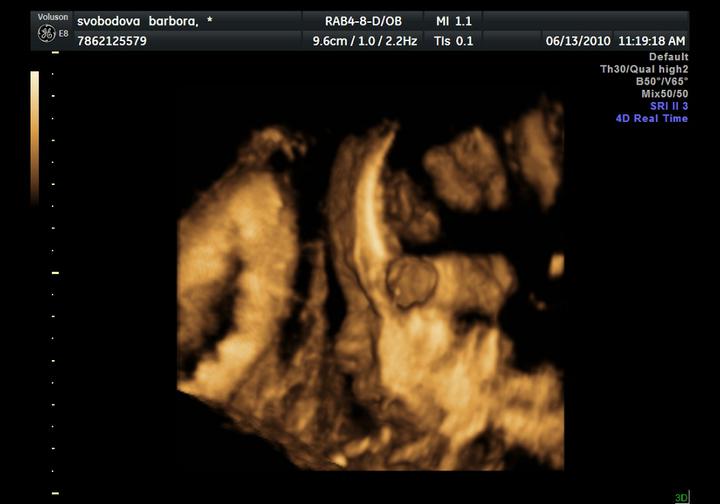

UZ byl naprosto úžasný zážitek, Adámek si cpal ručičky do pusinky, do nosánku, mrknul na nás, a ve finále ukázal fakáče 🙂

dneska jsme byli na velkém UZ, Adámek potvrzen a máme 414 g a asi 20 cm, odpovídáme 21+4, krásně rosteme 🙂